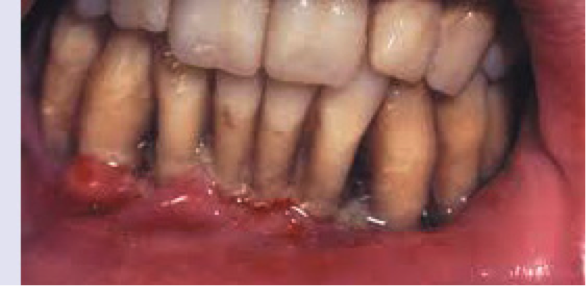

Χαρακτηρίζεται από έντονο πόνο και... πληγές στις παρυφές των ούλων που βρίσκονται μεταξύ των δοντιών (μεσοδόντια ούλα). Τα ούλα καλύπτονται από ψευδομεμβράνες, αιμορραγούν εύκολα ενώ παρουσιάζεται κακοσμία και συχνά μεταλλική γεύση.

H οξεία ελκονεκρωτική ουλίτιδα αποτελεί μία ξεχωριστή πάθηση των ούλων που δεν οφείλεται αποκλειστικά σε πλημμελή στοματική υγιεινή και συσσώρευση της οδοντικής μικροβιακής πλάκας. Προδιαθεσικοί παράγοντες είναι η κακή στοματική υγιεινή, το κάπνισμα, η κακή διατροφή, αλλά κυρίως το ψυχολογικό στρες και η ανοσοκαταστολή (όταν το ανοσοποιητικό σύστημα του οργανισμού έχει καταπέσει). Η ελκονεκρωτική ουλίτιδα μπορεί να εμφανίζεται σε οξεία ή χρόνια μορφή με επαναλαμβανόμενα επεισόδια, να εξελίσσεται σε ελκονεκρωτική περιοδοντίτιδα, στοματίτιδα ή φαρυγγίτιδα ή να συνυπάρχει με τα νοσήματα αυτά. Στις αναπτυγμένες χώρες εμφανίζεται συνήθως σε νεαρούς ενήλικες. Εμφανίζεται και σε ασθενείς με AIDS.